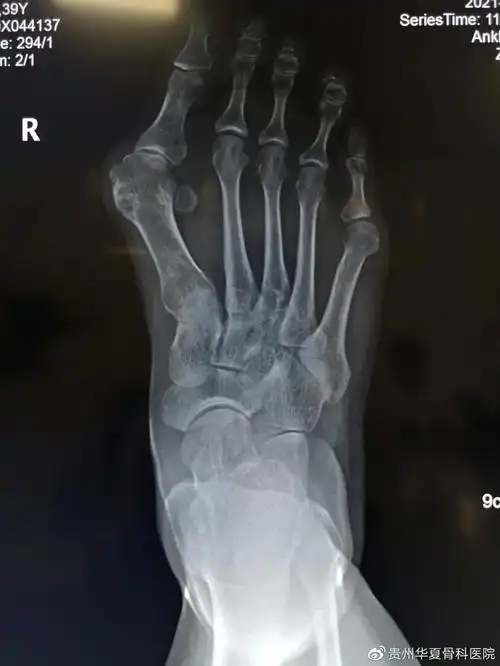

走路疼痛不敢穿凉鞋贵州华夏骨科医院有治疗大脚骨的好方法

x光片更直观了解大脚骨 如果单纯去掉凸起能否有效矫正拇外翻呢?